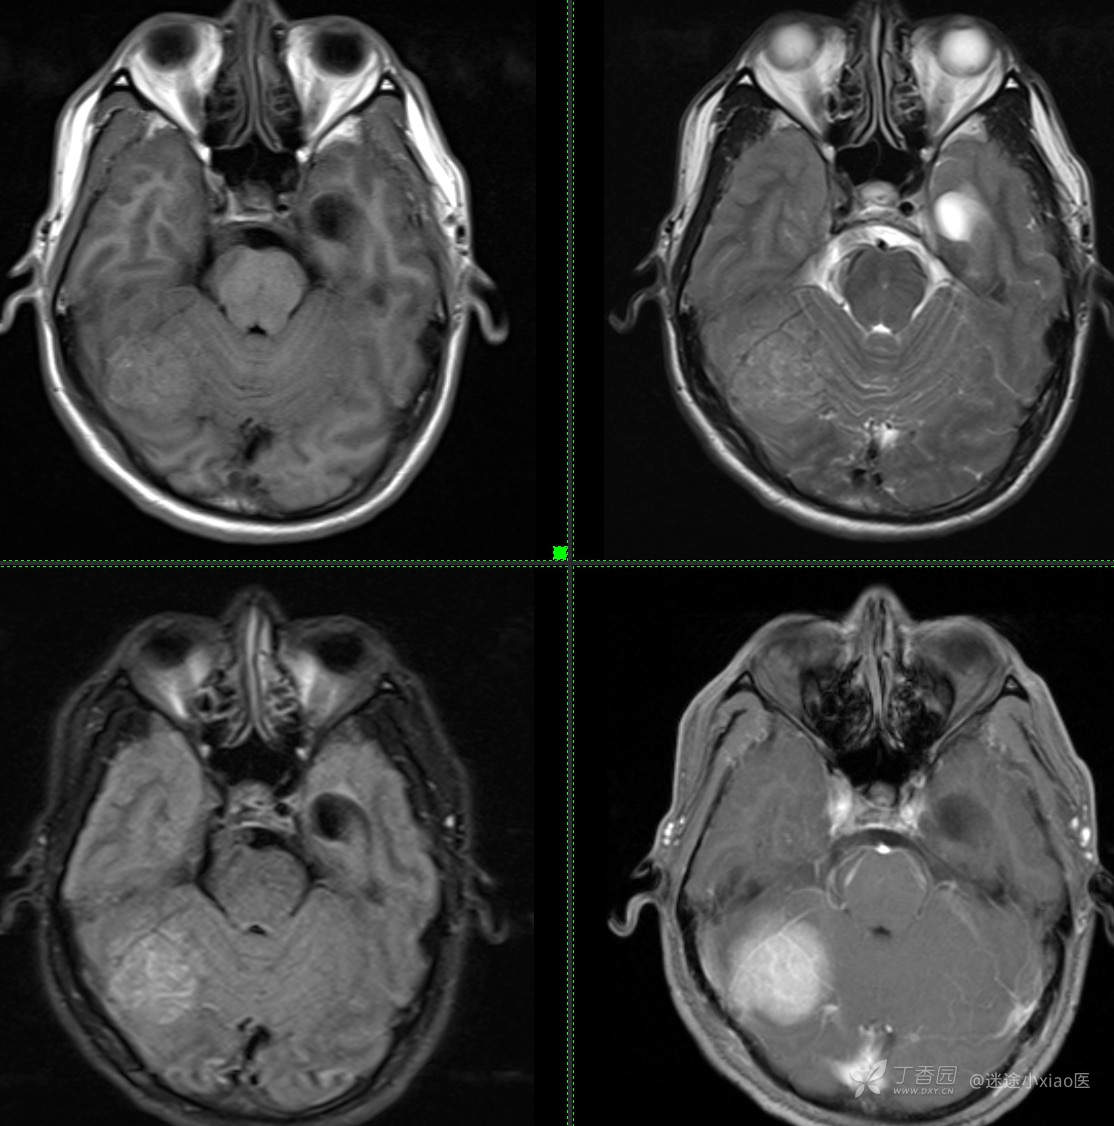

患者年龄:43

患者性别:男

简要病史:头痛3月余,查体无殊